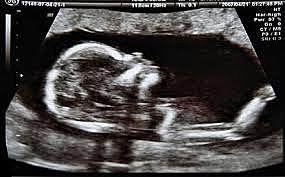

• Dr Douglas Howry

Dr Douglas Howry

Detectó estructuras de tejidos suaves al examinar los reflejos producidos por el ultrasonido en diferentes interfases.

• Howry y Bliss

Howry y Bliss

Publicaron imágenes bidimensionales del antebrazo, en vivo, por ultrasonido.

• Dr. Donald

Dr. Donald

Inició los estudios obstétricos a partir de los ecos provenientes del cráneo fetal.

-Donald desarrolló el primer scanner automático(ecógrafo), que resultó no ser práctico por lo costoso.